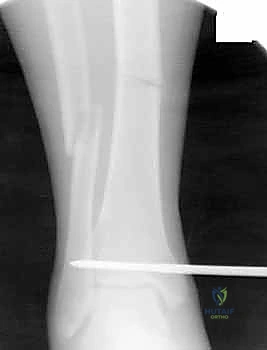

يبدأ التشخيص بالفحص السريري الدقيق لتقييم حالة الجلد، النبض، والأعصاب. يتبع ذلك إجراء الأشعة السينية (X-rays) من زوايا متعددة لتحديد موقع وشكل الكسر بدقة. في حالات الكسور المعقدة أو التي تمتد إلى مفصل الركبة أو الكاحل، يطلب البروفيسور هطيف إجراء أشعة مقطعية (CT Scan) للحصول على صورة ثلاثية الأبعاد تساعد في التخطيط الجراحي الدقيق.

- الالتئام العظمي (Bone Union): يكتمل الالتئام العظمي عادة بين الشهر الثالث والسادس. يتم تأكيد ذلك من خلال صور الأشعة السينية الدورية في عيادة البروفيسور.